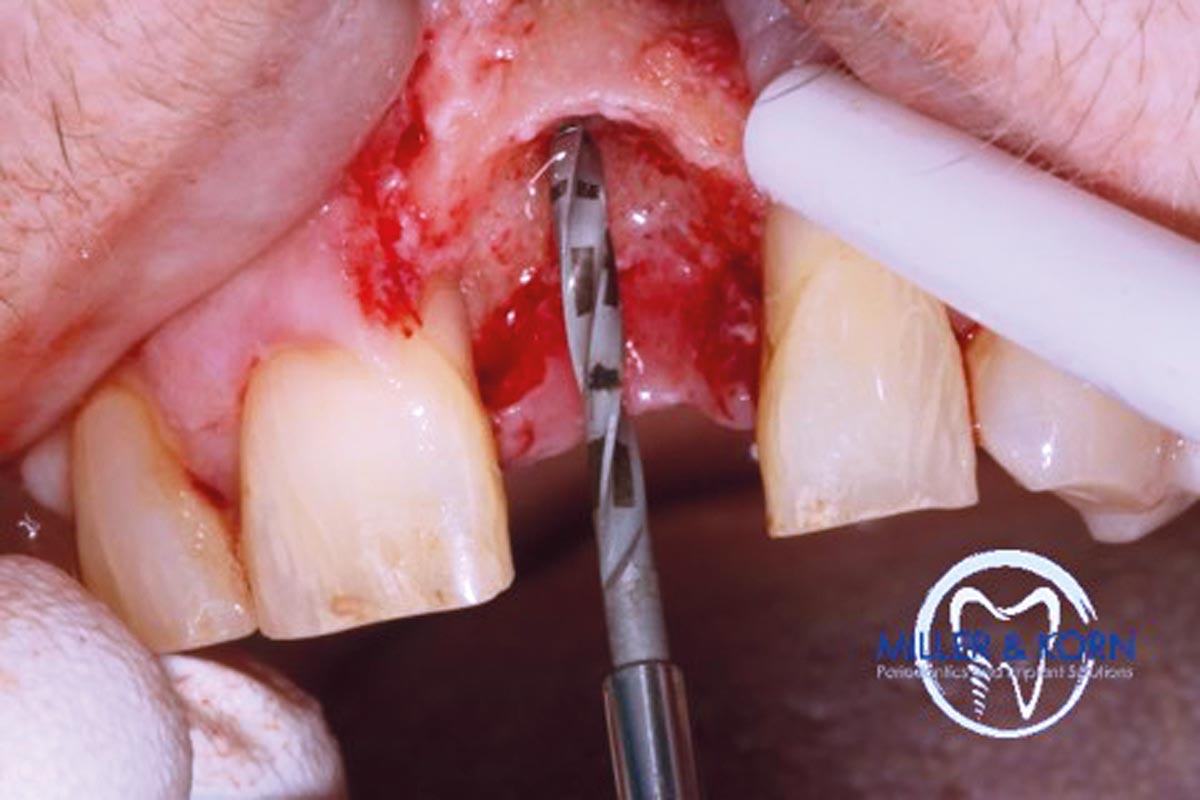

10/39 - Pilot drilling with a 2.2 mm twist drillImmediate implant placement and correction of horizontal and vertical bone loss using an allograft bone ring, cerabone® and Jason® membrane - Drs. Miller and Korn